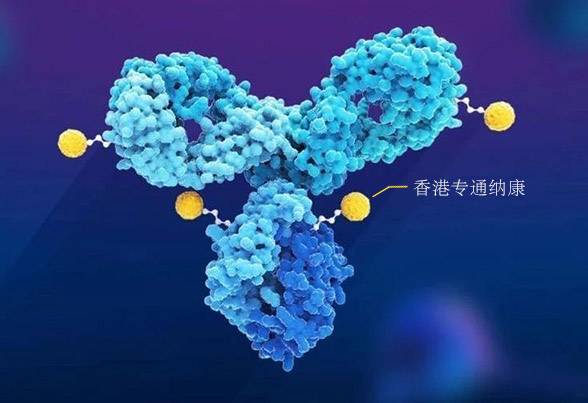

目前有100多种ADC正在进行临床试验。大多数ADC已从I期进展到II期。一些ADC的III期试验显示积极结果;截止2021年9月20日全球目前已有14款上市的ADC药物,治疗领域主要集中在血液瘤和实体瘤方面,并且主要是用于患者的后线治疗,包括晚期、复发/难治性以及转移性的肿瘤适应症。